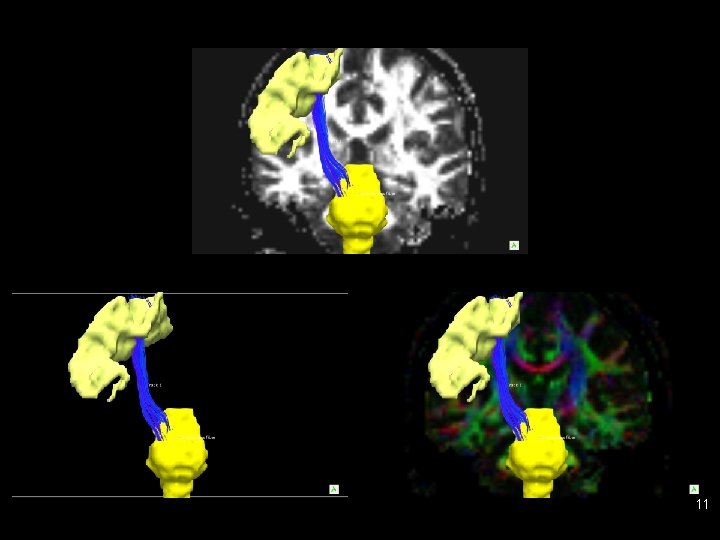

Tractography examples • Trackvis and Diffusion Toolkit (http: //www. trackvis. org/) 10

11

CST on (color) FA map 12